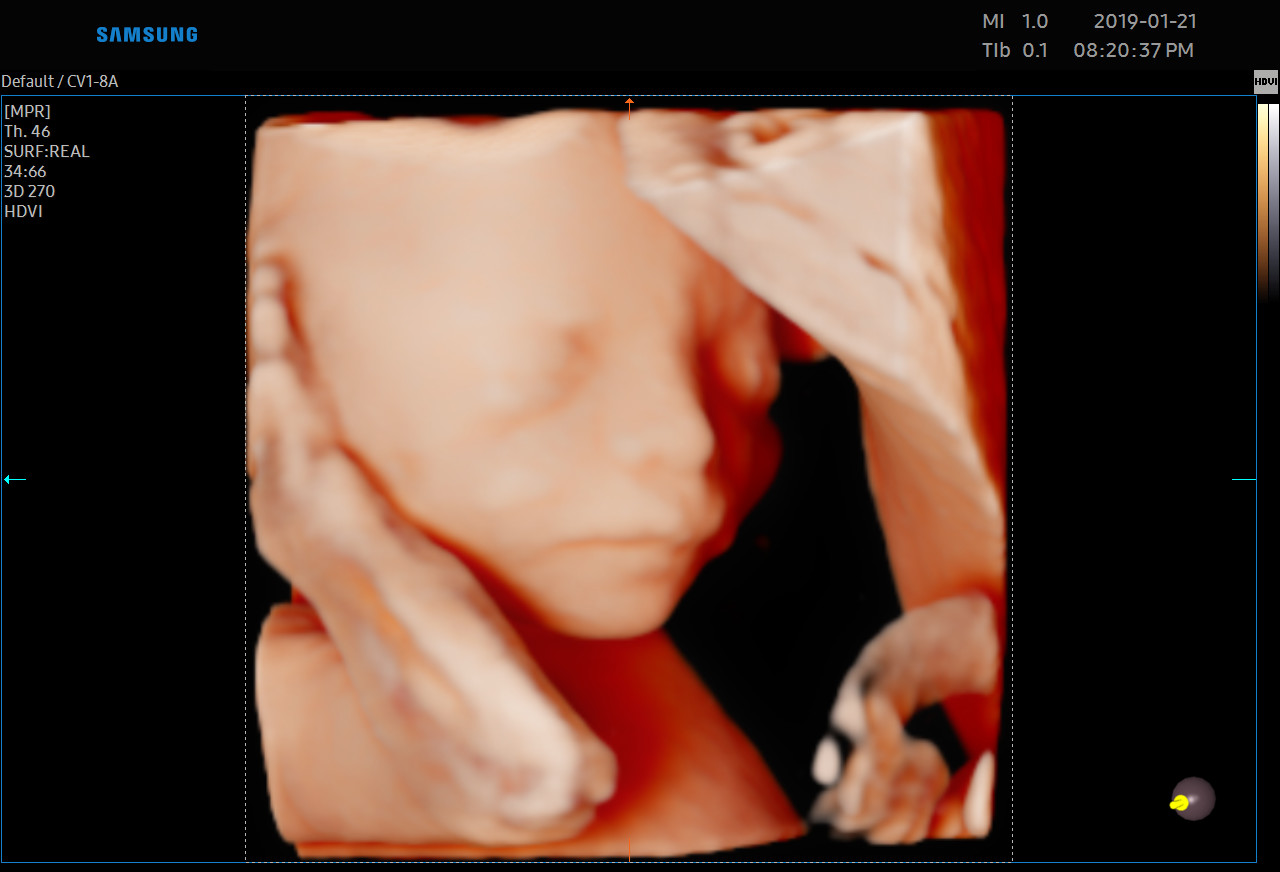

Każdą kobietę w ciąży otaczamy kompleksową opieką, czuwając nad jej zdrowiem oraz prawidłowym rozwojem płodu. Podczas regularnych wizyt, zlecamy odpowiednie badania laboratoryjne. Korzystając z najnowszej generacji aparatu USG, przeprowadzamy bardzo dokładną diagnostykę obrazową – łącznie z USG 3D/4D płodu.

• Najnowsza generacja aparatu USG pozwala na przeprowadzanie dokładnej diagnostyki obrazowej, diagnostyki przepływów (Doppler).